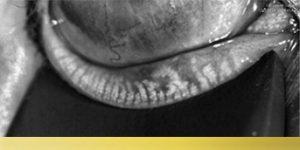

- Normal Gland Structure

- Significant Gland Loss

- Gland Shortening & Loss

- Severe Gland Loss

- High-resolution gland imaging (to check for gland atrophy)